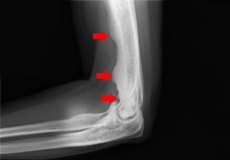

Multiple Hereditary Exostosis (Osteochondromas)

Multiple hereditary exostoses is a rare genetic condition in which an individual develops multiple bone tumors called osteochondromas, often on the growing ends of long bones or on the hips or shoulder blades. These tumors are non-cancerous but can cause growth problems in the affected bones.